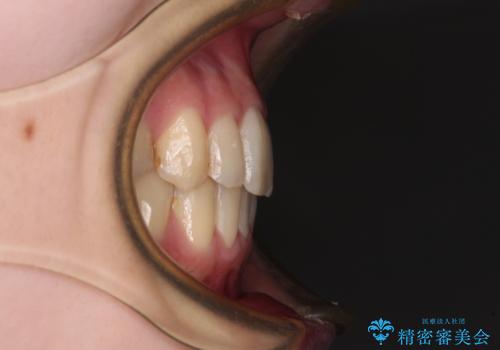

上顎骨の横幅が狭く、上下ともに内側に倒れ込んだ混み合った歯列となっていました。

急速拡大装置により上顎骨を側方に拡大し、ワイヤー装置により歯列を整えることとしました。